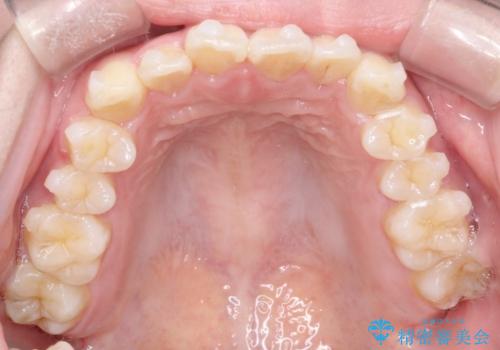

【インビザライン】前歯の凸凹をなおしたい

- 前歯のガタガタを主訴に来院されました。

インビザラインで綺麗な歯並びになり、患者さんには大変満足していただきました。